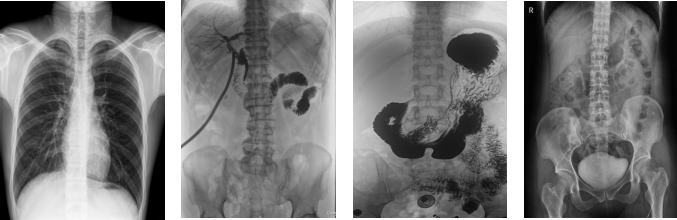

PLD8000C數(shù)字胃腸DR機(jī)全面突破傳統(tǒng)X射線攝影透視理念,成像部件采用新型動(dòng)態(tài)平板探測(cè)器,輕松解決數(shù)字?jǐn)z影、數(shù)字透視、數(shù)字造影等功能,并使數(shù)字透視獲得超大尺寸和清晰的圖像效果。滿足放射科、體檢中心、影像中心、內(nèi)科、婦科、外科、急診科、骨科、創(chuàng)傷科、消化科等科室的各種臨床檢查需求。如果您想采購(gòu)這款數(shù)字胃腸DR機(jī),歡迎咨詢400-025-6366。